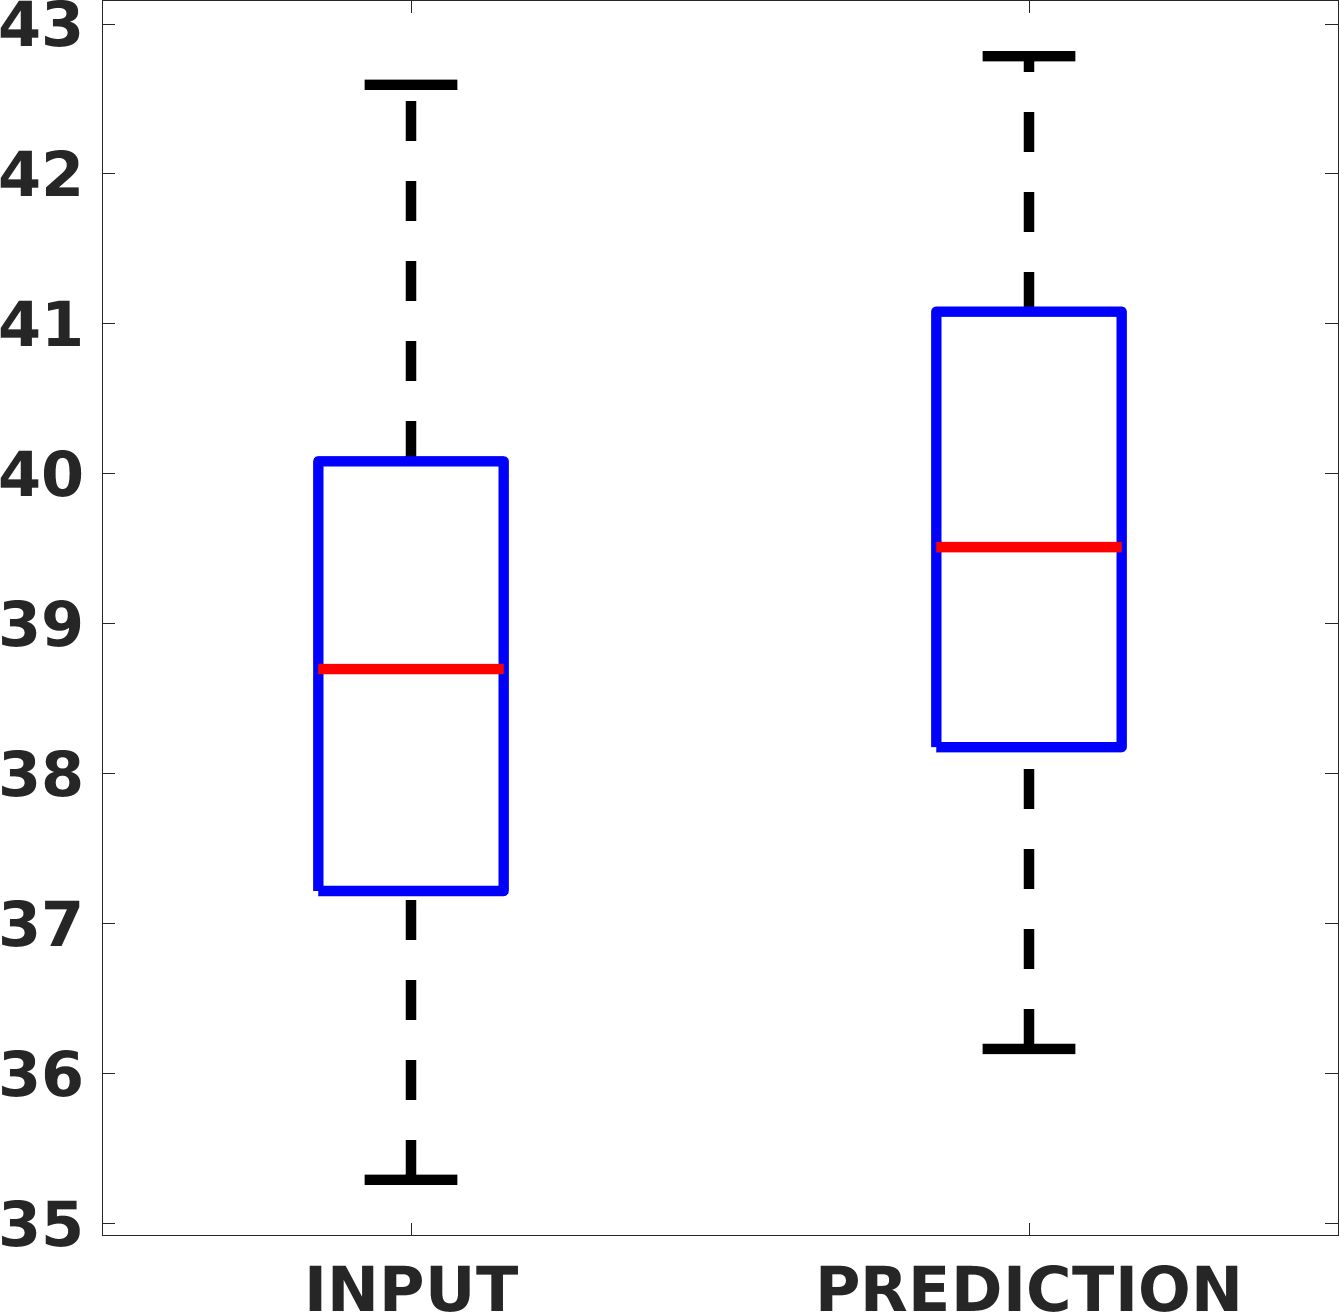

Fig. 7(a-b-c, left) shows the box plot of the statistics of the PSNR on three different anatomical districts, comparing the target images with the prediction and the cubic convolution, respectively. The metrics are computed on a data set of 200 images of the same district and with the same up-sampling factor. We report that the PSNR median value improves of on obstetric 2X raw images, on cardiac 2X raw images, and on abdominal raw 4X images.

Fig. 7(a-b-c, right) shows the histogram of the absolute value of the error with respect to the target image, of the prediction and Cubic convolution results, respectively. The histograms show the number of pixels where the prediction error is lower than 5 (i.e., the first bin of the histogram), which means very similar to the target when visually analysing the images. From the Cubic convolution to the predicted images, this value increases of on obstetric 4X raw images, on cardiac 4X raw images, and on abdominal 4X raw images.

Fig. 8 shows the box plot of the SSIM (a-b-c, left) and MAE (a-b-c, right) quantitative metrics, as performed for PSNR metric. Also, these metrics show that our method improves the results of Cubic convolution both in terms of average value and variability. For example, the SSIM median value improves of on obstetric 4X images and the MAE median value improves of on cardiac 2X images.

Fig. 17 (left) shows the box plot of the quantitative metrics, comparing the target images with the prediction and the Cubic convolution, respectively. The PSNR metric is computed on a data set of 200 images, belonging to the same district, and with the same up-sampling factor. Analysing the obstetric anatomical district and concerning the corresponding raw images (Fig. 7 (a, left)), the denoising allows the network to significantly improve the results of the up-sampling and the prediction. In particular, comparing the target images with the predicted images, the median PSNR value of obstetric 2X denoised images is 51.8, compared to the median PSNR value of obstetric 2X raw images which is 36.9.